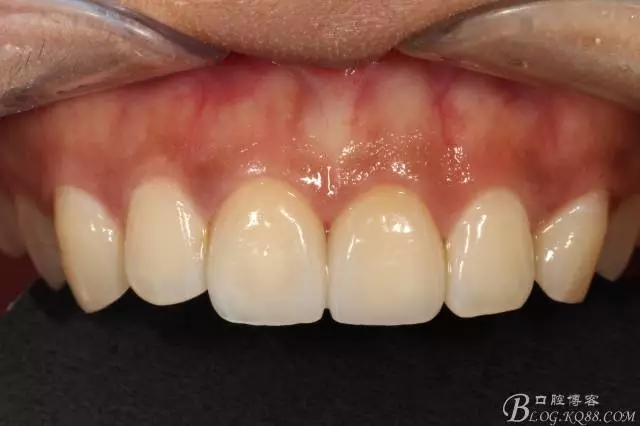

試戴

試戴局部放大

粘接完成即刻照

即刻照局部放大